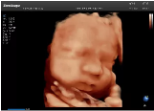

容積探頭是在二維圖像的基礎(chǔ)上,將連續(xù)采集的空間分布位置,經(jīng)過計算機(jī)重建算法,從而獲得完整的空間形態(tài)。

適用于:胎兒面部、脊柱和肢體等。

優(yōu)勢特點:快速獲取、掃查連續(xù)均勻、解剖結(jié)構(gòu)顯示為容積數(shù)據(jù)、準(zhǔn)確進(jìn)行容積測量。